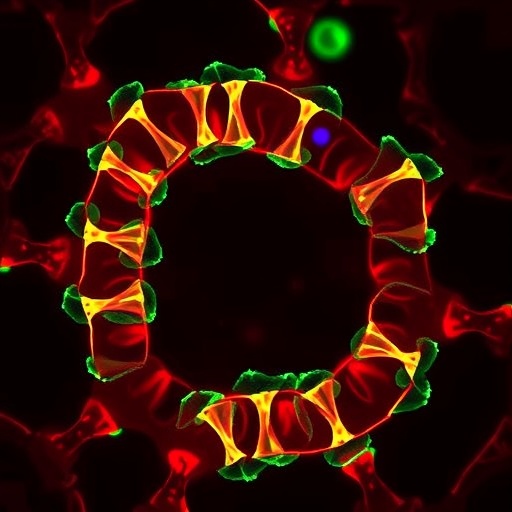

The innovative aspect of this study lies in harnessing nanotechnology to deliver ferroptosis inducers selectively to CAFs within the colorectal tumor microenvironment. By engineering nanocarriers that can navigate and penetrate the dense stromal architecture, the researchers ensured that the ferroptosis-inducing compounds reached their cellular targets effectively, minimizing off-target effects and systemic toxicity. This nano-enabled precision therapy epitomizes the convergence of molecular oncology and materials science, opening new therapeutic avenues that were previously inaccessible.

Mechanistically, the nanotherapy disrupts the metabolic and redox homeostasis in CAFs, precipitating an iron-catalyzed cascade of lipid peroxide accumulation. This not only induces ferroptotic cell death in the fibroblasts but also reverses the immunosuppressive landscape they maintain. The ablation of CAFs alleviates dense extracellular matrix deposition and diminishes inhibitory cytokines, thereby reawakening anti-tumor immune surveillance and enhancing the infiltration and activity of cytotoxic T cells within the tumor bed.